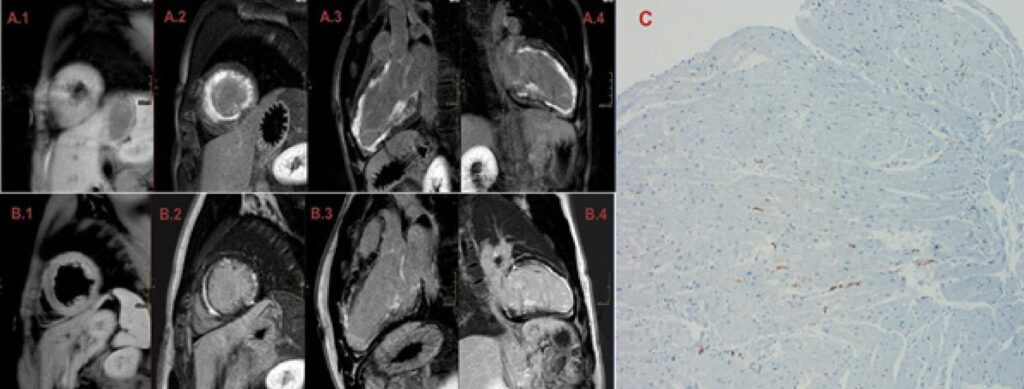

Etiological identification of young patients with heart failure should always be a medical goal. In this scenario, infectious myocarditis is a possible diagnosis and, when it occurs, it has a benign course in the majority of cases. However, congenital heart diseases or familial forms of cardiomyopathy should be considered in differential diagnosis and/or concomitantly, particularly in more severe presentations of myocarditis. In these cases, in addition to specific investigation for myocarditis, which may include clinical evaluation, imaging exams, laboratory tests, and endomyocardial biopsy with viral agent testing in myocardial tissue, genetic study is also worth considering. Associated etiologies can have an impact on clinical presentation and evolution, but data are still scarce, which means that there is still a gap to be explored in the literature. In this report, we describe the case of a young man with cardiogenic shock secondary to myocarditis caused by Epstein Barr virus (EBV), which led to identification of a pathogenic mutation in the PKP2 gene.